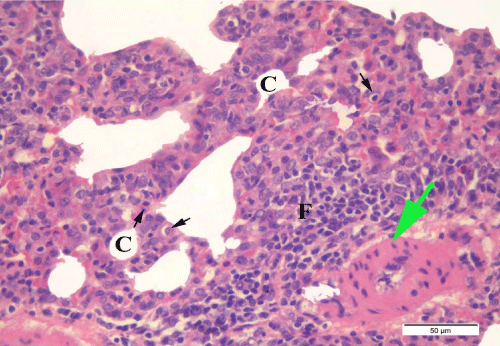

| Figure 8: A photomicrograph of a DEHP treated rat alveolar tissue showing collapsed alveoli (c). Thickened pulmonary vascular wall (green arrow), inflammatory cell infiltration (F) as well as necrotic type II pneumocytes with pyknotic nuclei (black arrow) are also shown. (H & E x400). |